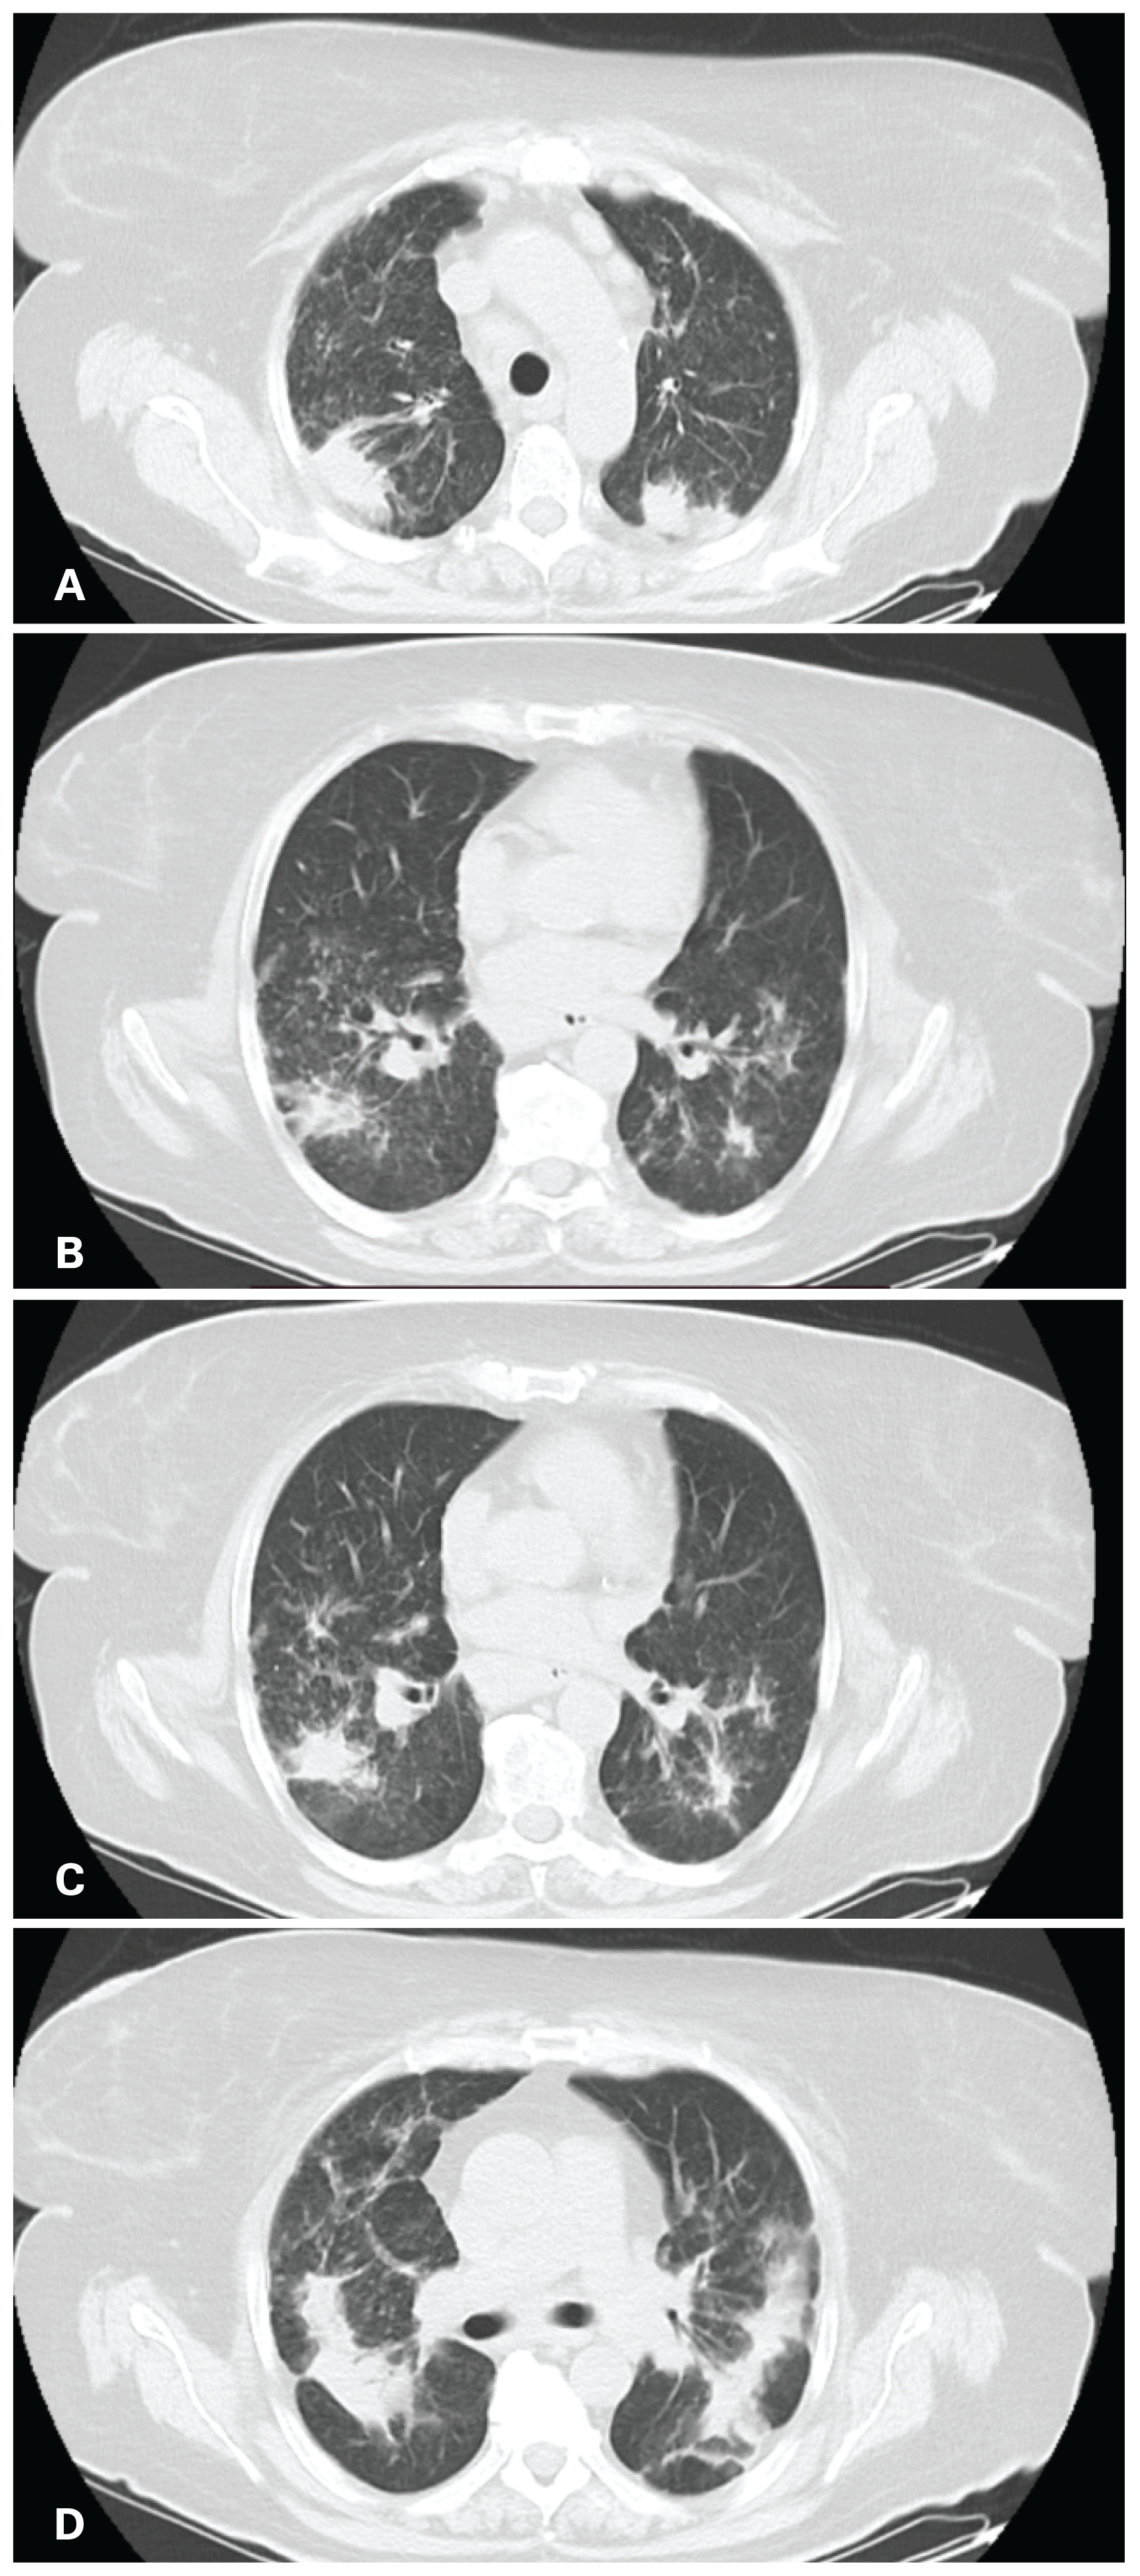

A 65-year-old female of German origin, current smoker, without occupational exposure to inhaled substances, was referred to our institution with fatigue, thoracic pain in the interscapular area and joint pain for the past 3 months. Her past medical history included diabetes mellitus type II with symptoms of diabetic neuralgia and dyslipidemia, for which she was treated with insulin glargine, sitagliptin, gabapentin and tramadol/acetaminophen. During the past three months the patient underwent a series of medical examinations, one of which was chest CT as part of the investigation for her fatigue and chest pain. High resolution chest computed tomography (HRCT) revealed mediastinal lymphadenopathy in stations 2, 3, 4, 5, 7 and 10 (Figure 1), along with bilateral patchy infiltrates in the pulmonary parenchyma (Figure 2).